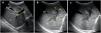

An abdominal ultrasound scan revealed hepatomegaly with periportal hypoechogenicity around the main portal vein and its branches (Figs. 1 and 2), and mild splenomegaly with multiple accessory spleens in the hilum (Fig. 3). The patient was referred to the corresponding referral hospital due to suspicion of myeloproliferative disease, where he received a diagnosis of acute myeloid leukaemia.

Oblique transverse plane of the hypochondrium obtained with a convex probe at the level of the epigastrium, showing: a) Homogeneous echogenicity of hepatic parenchyma (H) with normal appearance of right portal vein (PD), left portal vein (PI) and gallbladder (VB) in a healthy patient; b) Heterogeneous echogenicity of hepatic parenchyma (H1), right portal vein (PD1) and left portal vein (PI1) with a hypoechoic halo (M) in patient with acute myeloid leukaemia; c) Similar image in the same patient, without references to allow better visualization of the aforementioned structures.